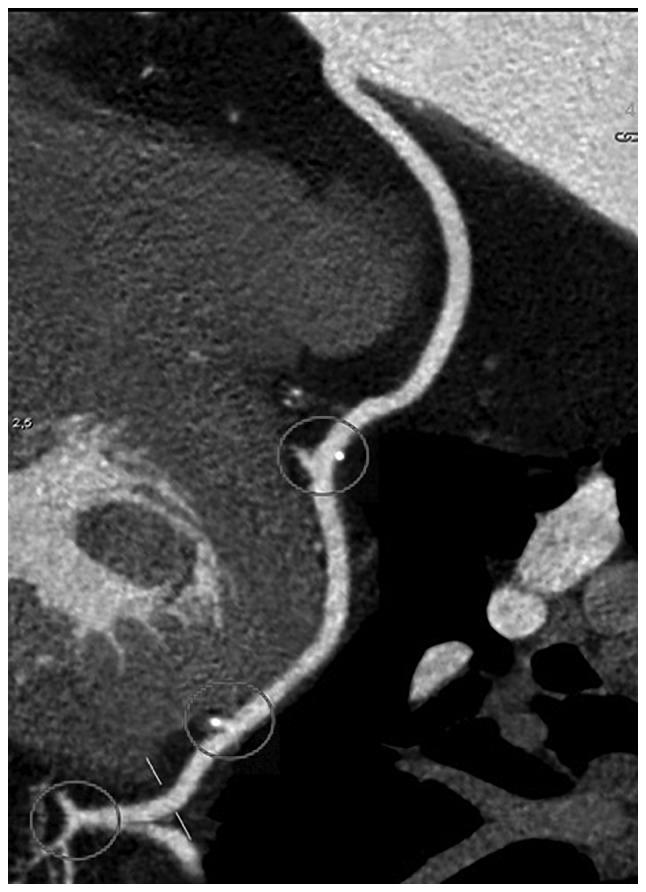

The aim of the current study was to identify surgical factors associated with long-term patency of grafts used in coronary artery bypass grafting (CABG). The present study analyzed data from 127 patients who underwent CABG at our institute between 2000 and 2006 and presented for ambulatory examination and coronary computed tomography angiography evaluation of graft patency in 2016 (139.78±36.64 months post-CABG). The 127 patients received 340 grafts (2.68 grafts/patient) and 399 distal anastomoses (3.14 anastomoses/patient), 220 (55.14%) with arterial grafts and 179 (44.86%) with saphenous vein grafts. Graft patency varied according to coronary territory, proximal anastomosis type ( graft, composite graft, graft anastomosed to the ascending aorta), Y anastomosis angle (47.21° for patent arterial grafts vs. 56° for occluded), and distal anastomosis angle (in sequential anastomoses irrespective to graft type, 48.60° for patent side-to-side anastomosis vs. 53.97° for occluded, 65.12° for patent end-to-side anastomosis vs. 90.80° for occluded; in single end-to-side anastomosis of arterial grafts, 39.46° for patent and 44.94° for occluded). A single end-to-side anastomosis angle 60° or greater was associated with a 5.149 occlusion odds ratio (OR) (P<0.001) for arterial grafts. Venous grafts were not sensitive to single end-to-side anastomosis angle. In conclusion, a small anastomosis angle for proximal Y and distal anastomoses is associated with a higher long-term patency of the free graft. Radial artery grafts registered higher patency rates when anastomosed to the ascending aorta compared with composite grafting with the left internal thoracic artery, whereas right internal thoracic artery (RITA) anastomosed to the right coronary territory is associated with a lower patency rate compared with free RITA used to revascularise the anterolateral or circumflex territory in composite grafting.

本研究的目的是确定与冠状动脉旁路移植术(CABG)中使用的移植物长期通畅相关的手术因素。本研究分析了2000年至2006年间在我院接受CABG手术,并于2016年接受门诊检查及冠状动脉计算机断层血管造影评估移植物通畅情况的127例患者的数据(CABG术后139.78±36.64个月)。127例患者共接受了340处移植物(2.68处移植物/患者)和399处远端吻合(3.14处吻合/患者),其中动脉移植物220处(55.14%),大隐静脉移植物179处(44.86%)。移植物通畅情况因冠状动脉区域、近端吻合类型(移植物、复合移植物、吻合至升主动脉的移植物)、Y形吻合角度(通畅动脉移植物为47.21°,闭塞动脉移植物为56°)以及远端吻合角度(在序贯吻合中,与移植物类型无关,侧侧吻合通畅时为48.60°,闭塞时为53.97°;端侧吻合通畅时为65.12°,闭塞时为90.80°;在动脉移植物的单端侧吻合中,通畅时为39.46°,闭塞时为44.94°)而异。动脉移植物单端侧吻合角度≥60°时,闭塞比值比(OR)为5.149(P<;0.001)。静脉移植物对单端侧吻合角度不敏感。总之,近端Y形吻合和远端吻合的吻合角度较小与游离移植物较高的长期通畅率相关。与左胸廓内动脉复合移植相比,桡动脉移植物吻合至升主动脉时通畅率更高,而右胸廓内动脉(RITA)吻合至右冠状动脉区域时,与复合移植中用于前外侧或回旋支区域血运重建的游离RITA相比,通畅率较低。